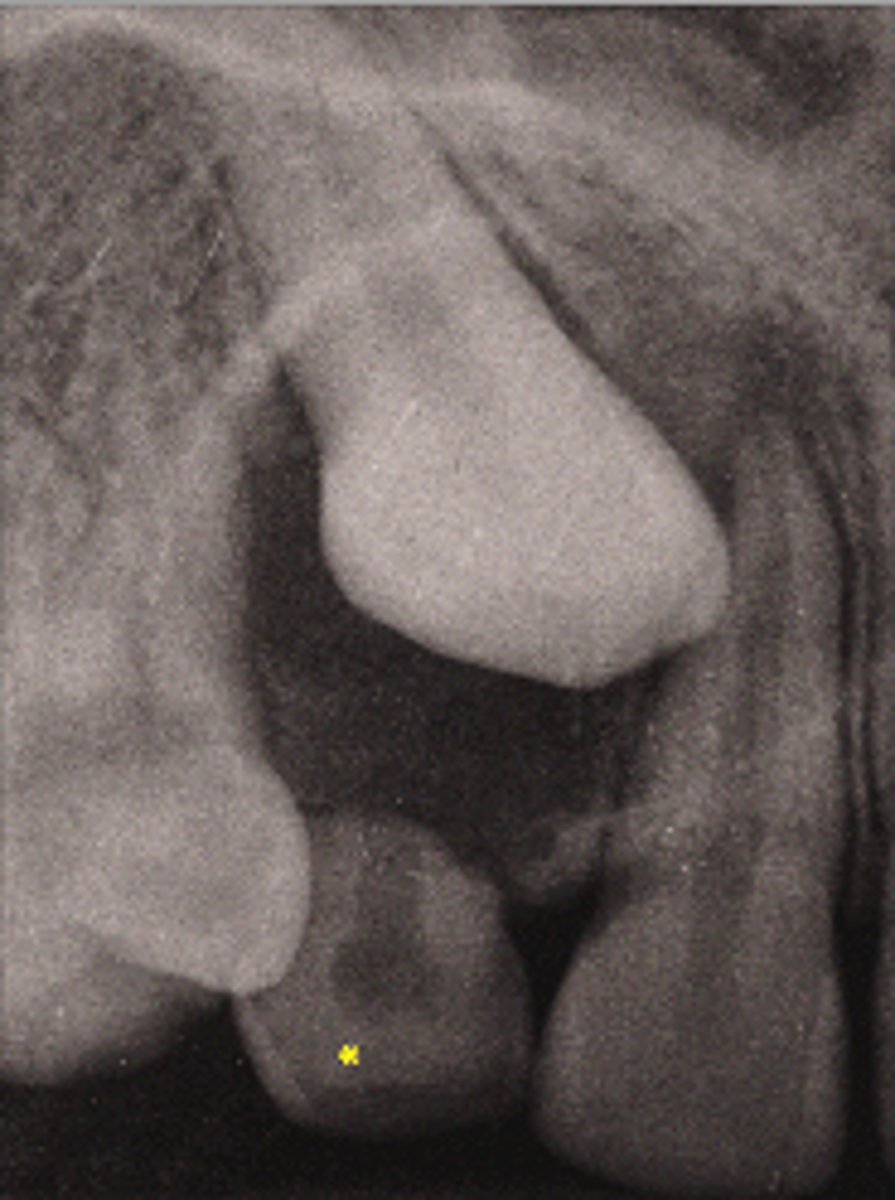

Dentigerous cyst

ID the cyst:

•Well defined and corticated periphery

•radiolucent

•Pericoronal (associated with crown of unerupted tooth)

•Usually envelops the crown symmetrically

•Usually unilocular

•Displacement of teeth/adjoining anatomical structures

•Displaces associated tooth in an apical direction

•Osseous expansion- of outer cortical boundary of the involved jaw